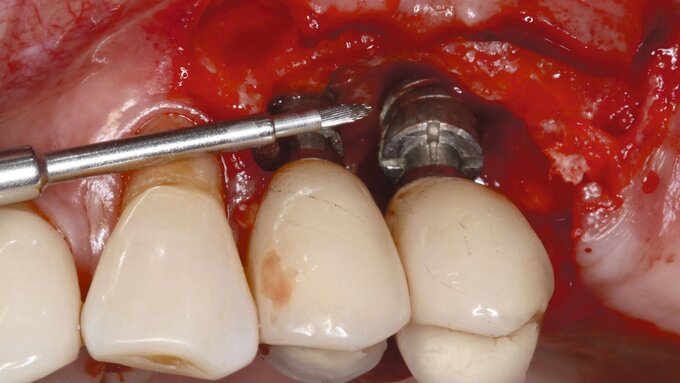

Bei den zweiteiligen Keramikimplantaten gibt es verschiedene Möglichkeiten, den enossalen Anteil mit dem Abutment zu verbinden. Neben klassisch verschraubten Verbindungen mit und ohne Metalleinsatz im Implantat (Abbildung), kommen auch geklebte Aufbauten zum Einsatz. Aber erreichen diese zweiteiligen Keramikimplantate auch über einen längeren Beobachtungszeitraum gute klinische Erfolgsraten?